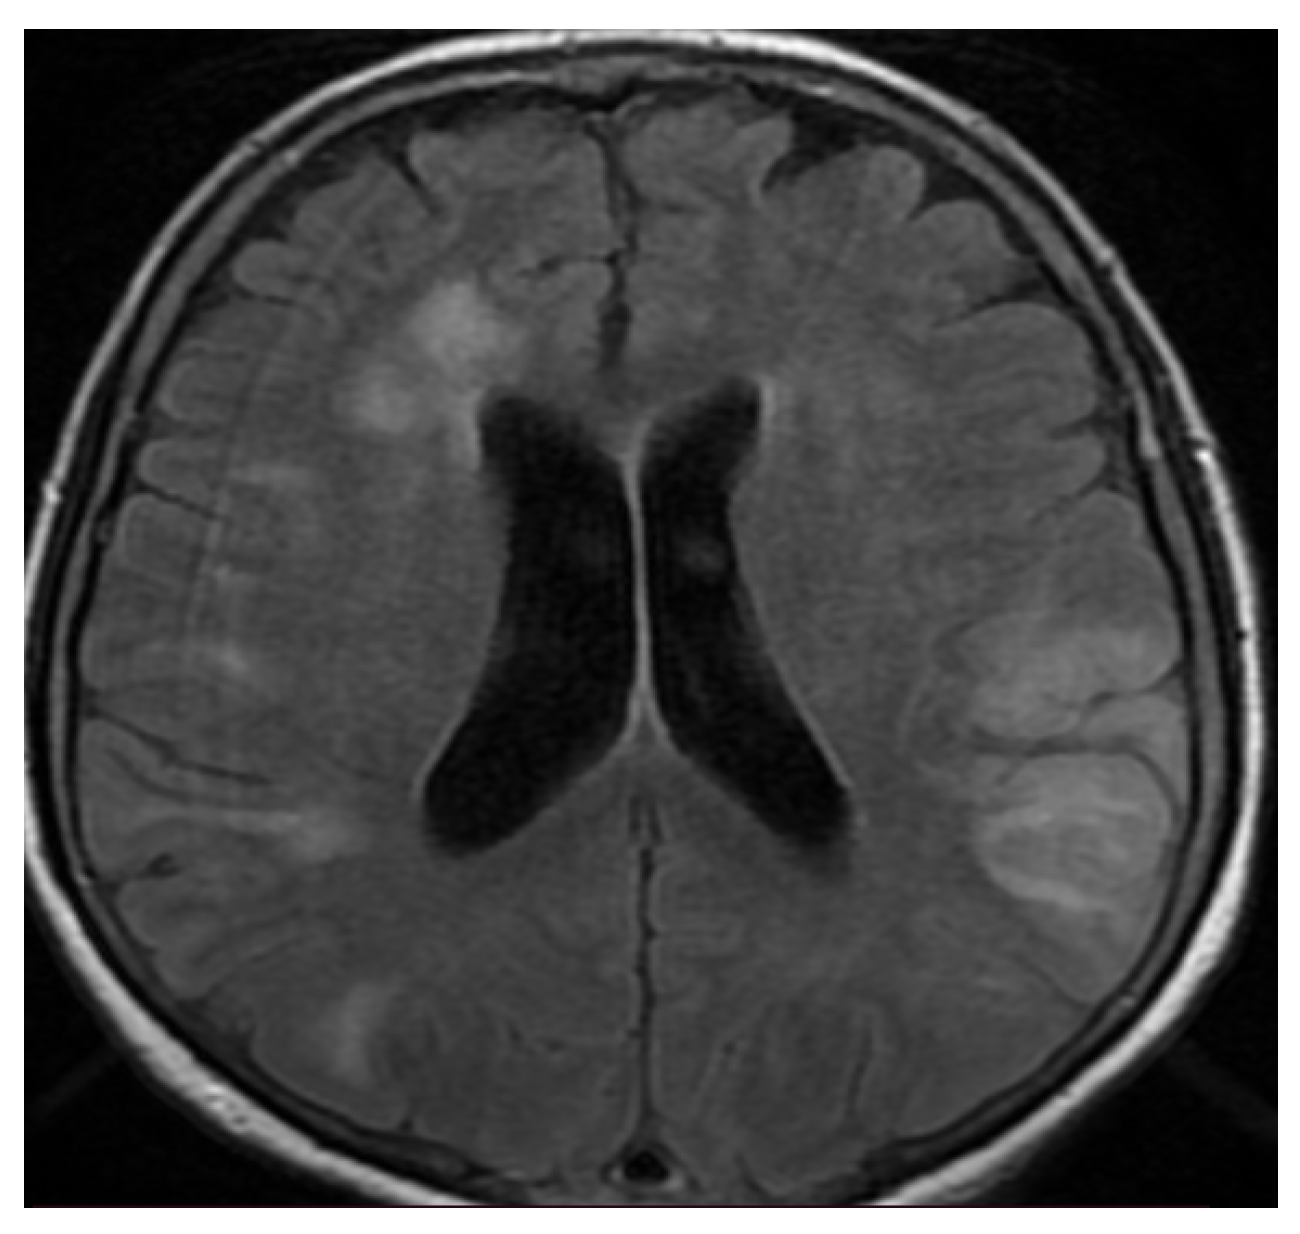

3.3. Neuroimaging